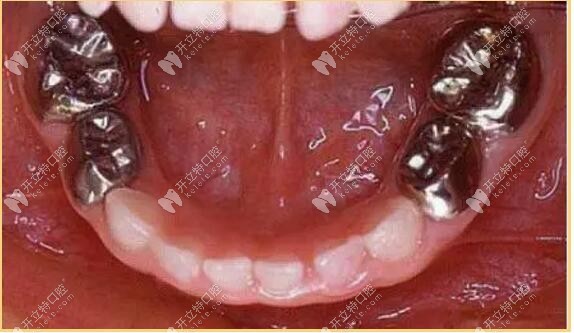

二、金屬預(yù)成冠

又叫不銹鋼冠,常用語乳牙磨牙治療,兒童不銹鋼乳牙欲成歡是一個預(yù)先塑性的、與牙齒貼合度比較高的金屬牙冠,用來套在乳牙上,保護(hù)牙齒并加強(qiáng)牙齒的強(qiáng)度,確保正常被恒壓替換。

金屬預(yù)成冠

金屬預(yù)成冠能有效防止充填物的脫落、繼發(fā)齲的產(chǎn)生和牙體組織的折裂,保證兒童的頜骨生長和繼承恒壓的替換。